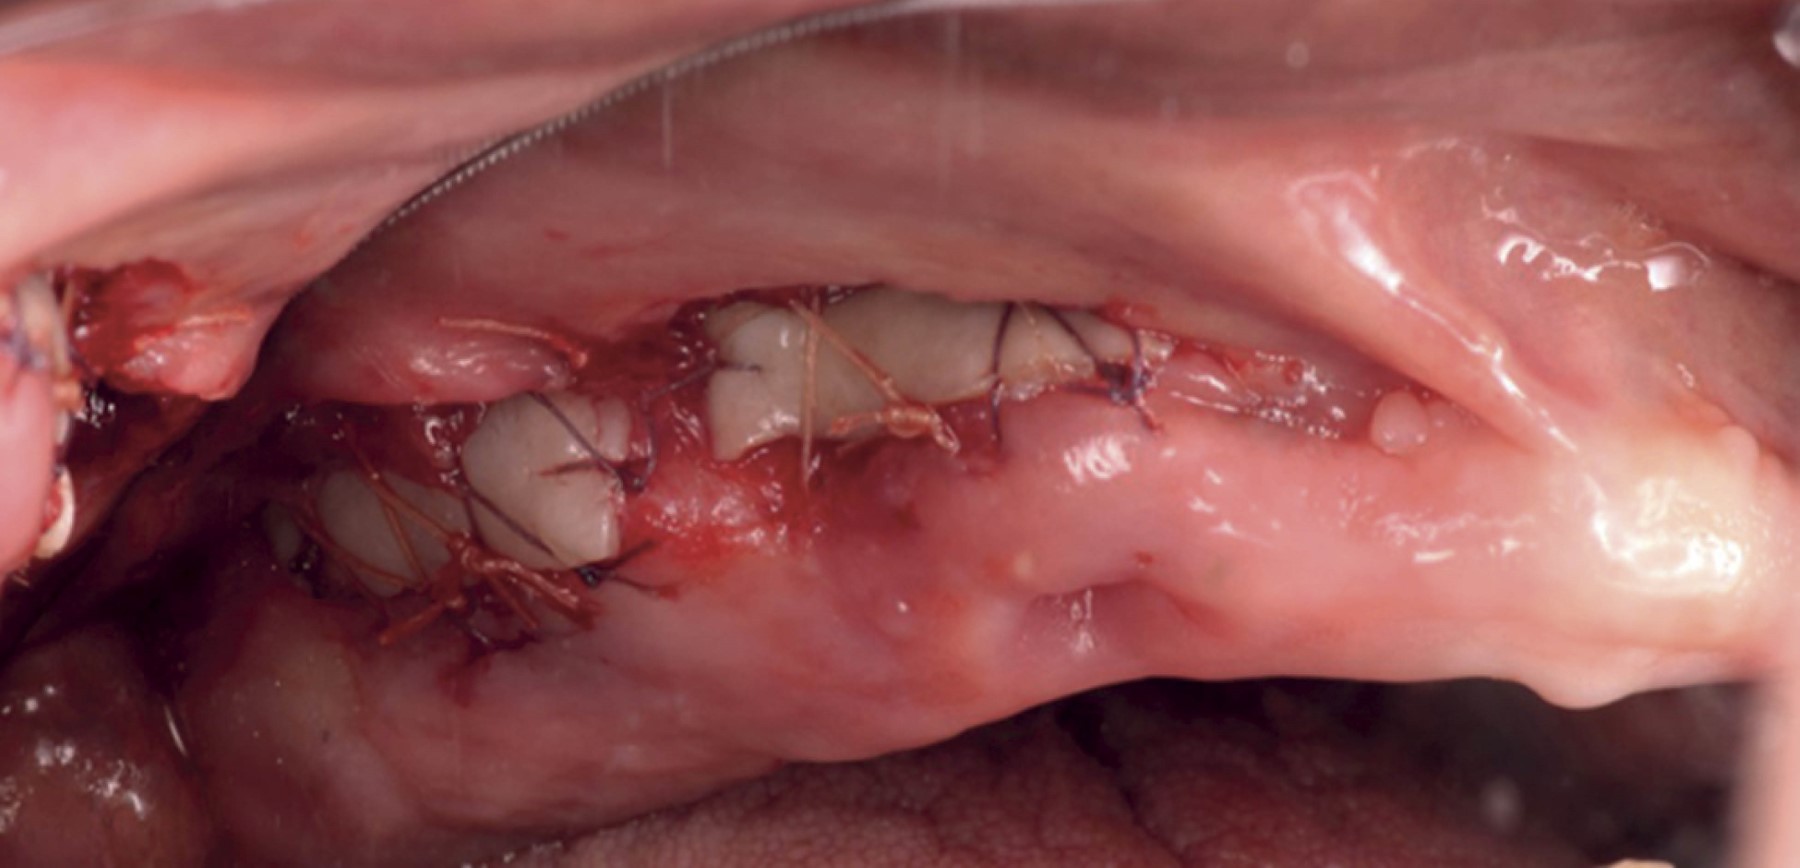

El procedimiento quirúrgico se llevó a cabo bajo anestesia local, mediante las técnicas de alveolares posteriores superiores, alveolares medios, técnica infraorbitaria en la zona receptora de la vestibuloplastia. Para la toma del IGL se anestesió mediante la técnica palatina mayor y nasopalatina. Se inició con una incisión a nivel de la línea mucogingival con descarga distal y mesial y posteriormente se continuó con la elevación de un colgajo parcial y la disección de las fibras musculares (Figura 2). Una vez preparado el lecho receptor, se procedió a la toma del IGL de la mucosa palatina y se realizó la disección del injerto para obtener un grosor de 1 mm aproximadamente (Figuras 3 y 4). Luego, se colocó el IGL en la zona receptora y se fijó mediante puntos simples con Vicryl 5.0 en los extremos del injerto al periostio, seguido de puntos en X fijados en el periostio en la zona apical y en la encía queratinizada hacia el reborde. Finalmente, se colocaron puntos simples para llevar el borde bucal de la herida hacia la porción más apical (Figura 5).

Figura 2